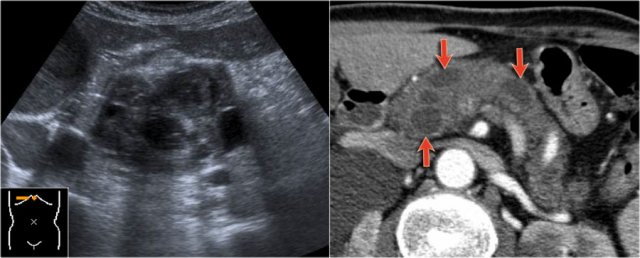

The CT-image shows a hypodense lesion in the pancreatic head.

This could be an adenocarcinoma, but the low density makes you think of a cystic tumor.

The microcystic appearance raises the possibility of a serous cystic neoplasm although there is no calcified scar.

On MRCP the cystic nature is better appreciated and there is a connection to a widened duct (blue arrow).

A detail nicely demonstrates that some of the mucus-filled branches are seen in cross-section and some longitudinally.